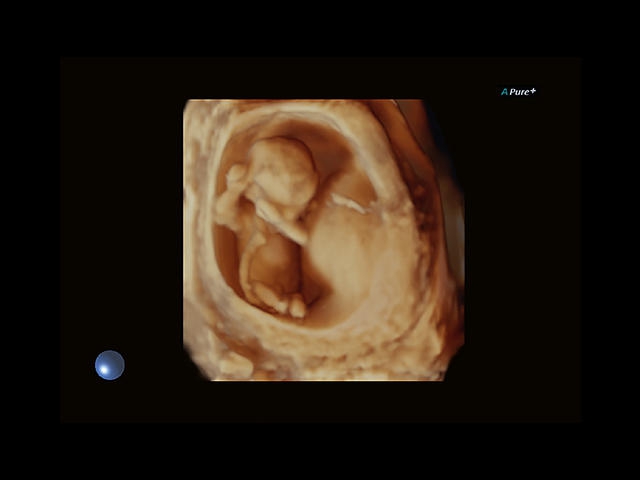

Aplio 500 – ультразвуковой сканер премиум класса, сочетающий в себе быстродействие диагностики и отличное качество визуализации. Более 30 датчиков на выбор, в т.ч. матричные, монокристаллические, 4D, эндоскопические для любых типов исследований. Ультразвуковой сканер позволяет изучать анатомические структуры в высоком разрешении.

Обновленная версия легендарного УЗ-сканера. Стационарный аппарат экспертного класса Aplio 500 Toshiba NEW, визуализирует анатомические структуры в высоком разрешении. Модель позволяет выявить микрокальцификаты, новообразования, нарушения в работе сердца, сосудов и мышц. Присутствует функция виртуальной эндоскопии, 4D-сканирования, эластометрии тканей, УЗИ с контрастированием. За повышение качества изображения отвечают технологии ApliPure и Superb Microvascular Imaging. Первая задействует возможности пространственного и частотного кодирования, формирует цельный визуальный ряд с сохранением клинических маркеров. Вторая улучшает отображение микрососудистого русла, используя доплеровский эффект. Модель оснащена 21-дюймовым монитором, имеет 4 активных порта. Возможно подключение педиатрических, интраоперационных, лапароскопических и чреспищеводных датчиков.

• Fly Thru. Виртуальная эндосонография обеспечивает построение трехмерной модели полостей, протоков и сосудов в рельном времени, облегчает организацию инвазивных процедур и динамических исследований. Посредством Fly Thru можно установить шунты и стенты, проводить точные оперативные вмешательства.